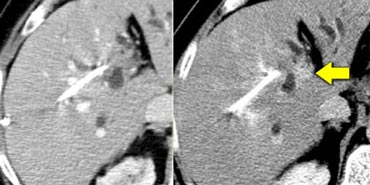

Cholangiocarcinoma: Non enhanced, arterial, portal venous and equilibrium phase. Cholangiocarcinoma: Non enhanced, arterial, portal venous and equilibrium phase.

First look at the images on the left and try to find good descriptive terms for what you see. Then continue.

The lesion on the left has the folowing characteristics:

• The lesion is hypodens in the arterial and portal venous phase with some peripheral enhancement.

• The lesion is hyperdense in the equilibrium phase indicating dens fibrous tissue.

• The lesion causes retraction of the liver capsule

The finding of an infiltrating mass with capsular retraction and delayed persistent enhancement is very typical for a cholangiocarcinoma.

Infiltrative cholangiocarcinoma does not cause mass effect, because when the stroma matures, the fibrous tissue will contract and cause retraction of the liver capsule.

There are not many tumors that cause retraction of the liver capsule, since most tumors will bulge.

The most common tumor that causes retraction besides cholangiocarcinoma is metastatic breast cancer.

The case on the left demonstrates how difficult the detection of ta cholangiocarcinoma can be.

Only on the delayed images at 8-10 minutes after contrast injection a relative hyperdense lesion is seen. This is the fibrous component of the tumor.